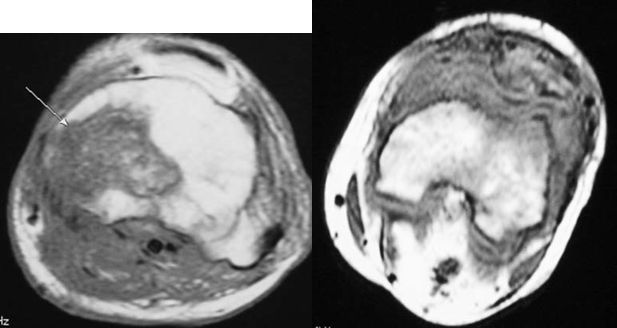

2、X线片(站立或负重位)示关节间隙变窄、软骨下骨硬化、和(或)囊性变、关节缘骨赘形成。

2、软骨下骨板硬化:软骨下骨板致密、硬化,负重软骨下骨质内可见囊性改变。

软骨下骨板硬化